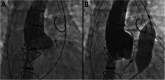

There is a growing appreciation for the adverse long-term impact of right-sided valvular dysfunction in patients with congenital heart disease. Although right-sided valvular stenosis and/or regurgitation is often better tolerated than left-sided valvular dysfunction in the short and intermediate term, the long-term consequences are numerous and include, but are not limited to, arrhythmias, heart failure, and multi-organ dysfunction. Surgical right-sided valve interventions have been performed for many decades, but the comorbidities associated with multiple surgeries are a concern. Transcatheter right-sided valve replacement is safe and effective and is being performed at an increasing number of centers around the world. It offers an alternative to traditional surgical techniques and may potentially alter the decision making process whereby valvular replacement is performed prior to the development of long-term sequelae of right-sided valvular dysfunction.